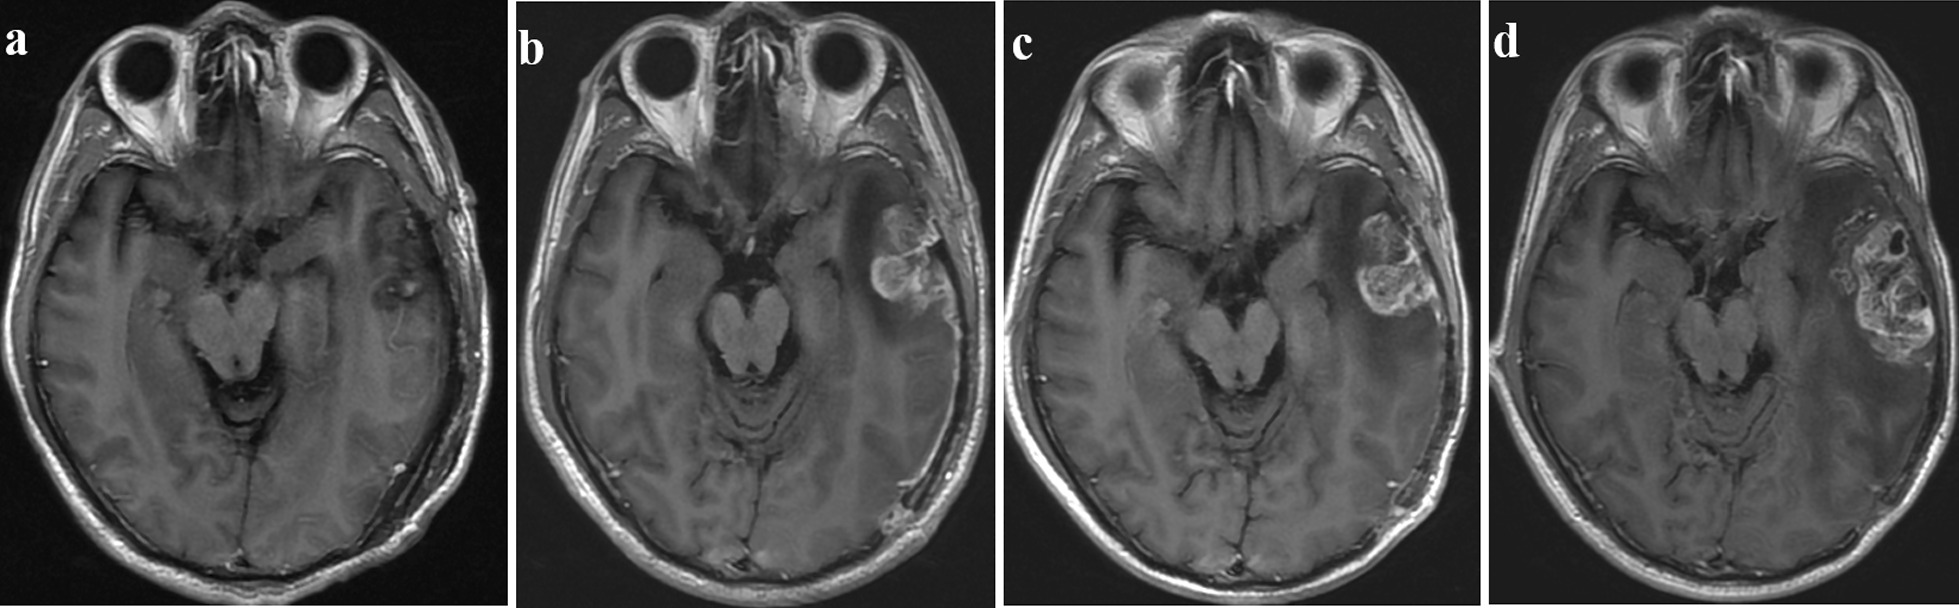

Figures 3 and 4 demonstrate representative patients withpseudoprogression and true progression onT1CE imaging, respectively. The pseudoprogression case (Fig. 3), in the absence of more interventions, showed a strengthened extent of the lesion and a reduced degree of enhancement. The case of true progression (Fig. 4) showed a marked increase in the extent of the enhanced lesions, which was confirmed by secondary surgical pathology as tumor recurrence.

Fig. 4.

T1CE images showing true progression in a 48-year-old male patient with GBM. (a) Postoperative MRI (within 24 h after surgery) showed that the tumor was completely resected. (b) Two months after CCRT, the new enhancement disappeared. After CCRT and at the (c) 6-and (d) 9-month follow-ups, the follow-up MR images demonstrated that the extension of the enhanced lesion increased. Recurrence was confirmed by second surgical pathology. (GBM: glioblastoma multiforme)